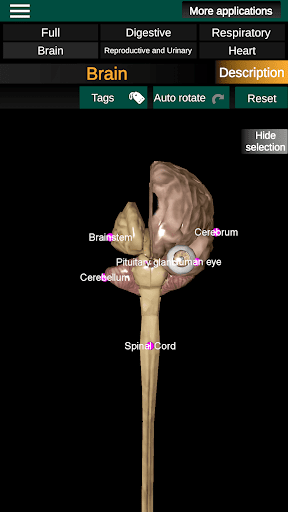

* Brain, which includes the brain, cerebellum, and brain stem.

* Easy to access and navigate (zoom, 3D rotation).

* Hide or show information.

* Descriptions of each organ.